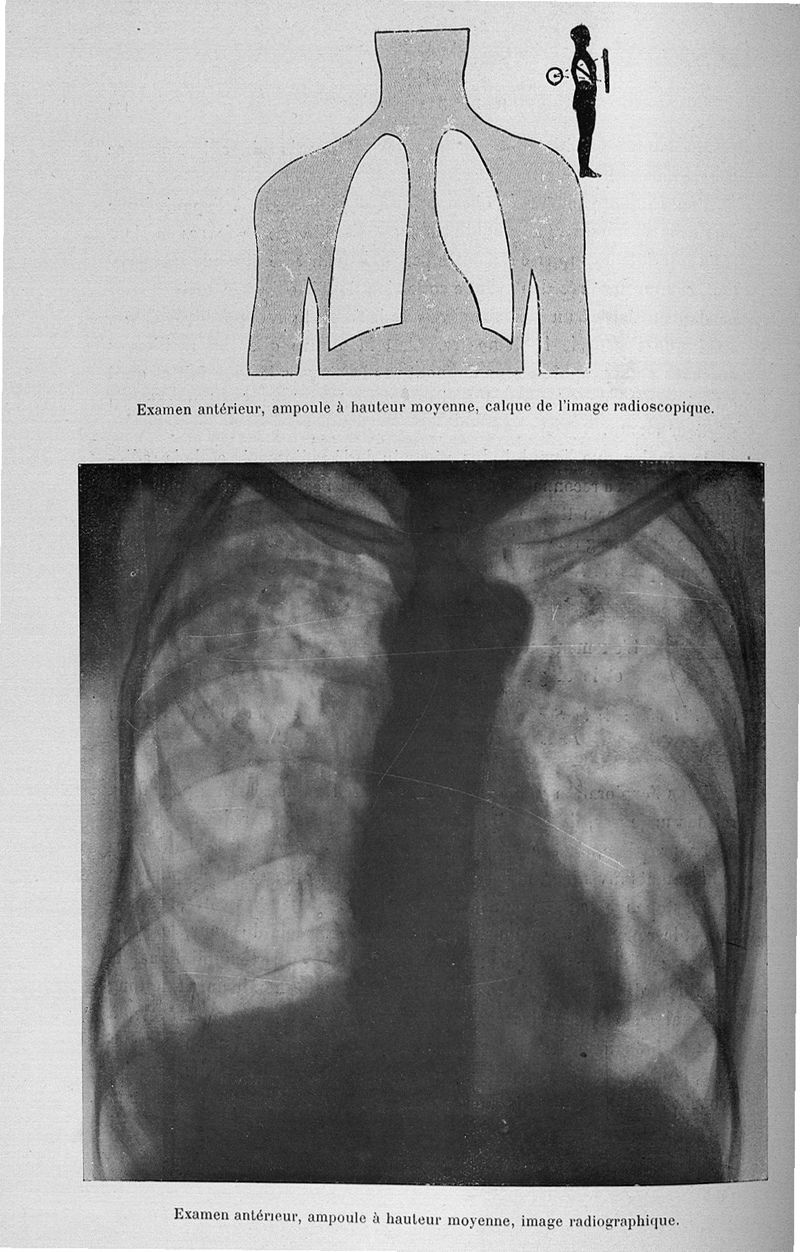

Béclère, Antoine Louis Gustave.

Exposé des travaux scientifiques

Paris, Masson, 1907.